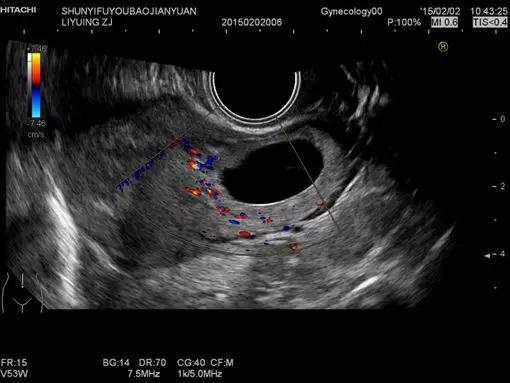

经阴道扫查(即阴式B超),是通过超声机上的腔内探头套上隔离套,将探头伸入阴道进行检查。由于探头位置接近子宫和卵巢,图像清晰分辨率高,检查结果较准确。

阴超频率比腹部常规用探头高,分辨率比腹部探头明显增强。探头在阴道内紧贴宫颈及后穹窿,不像腹部B超,声束要经过腹壁皮肤、肌肉、膀胱、肠道,所以盆器显示更清晰。尤其是对后位子宫、子宫内膜癌、子宫肌瘤、后盆腔肿块、卵泡监测、早期宫外孕(未破前)、早早孕、前置胎盘等观察,图象显示比经腹部B超明显清晰。对早早孕的检测,比腹式B超早发现5-7日。不需憋尿,为患者争取时间,且患者不受充盈膀胱之不适。

阴式B超在近两年得到迅速的发展,特别是在妇产科领域已经成为必不可少的检查手段之一,所以女性在出现一些妇科疾病的时候医生会结合腹式B超以及阴式B超来帮助诊断疾病。建议已婚女性常规可采用此方法检查。经阴道彩超不止非孕妇可以检查,孕妇也是可以检查的。

早孕期做经阴道超声能够提早1-2周观察到胎芽及胎儿的情况,而且探头分辨率高,贴近宫颈,所看到的图像更清楚。但是,有的孕妇肯定会担心早孕期做阴式B超是否会对宝宝不好,根据2019年中国医师协会超声医师分会编著的中国产科超声检查指南指出,目前没有证据证实早孕期阴式B超检查增加流产的风险,反而相较于腹式B超检查提高了诊断率。